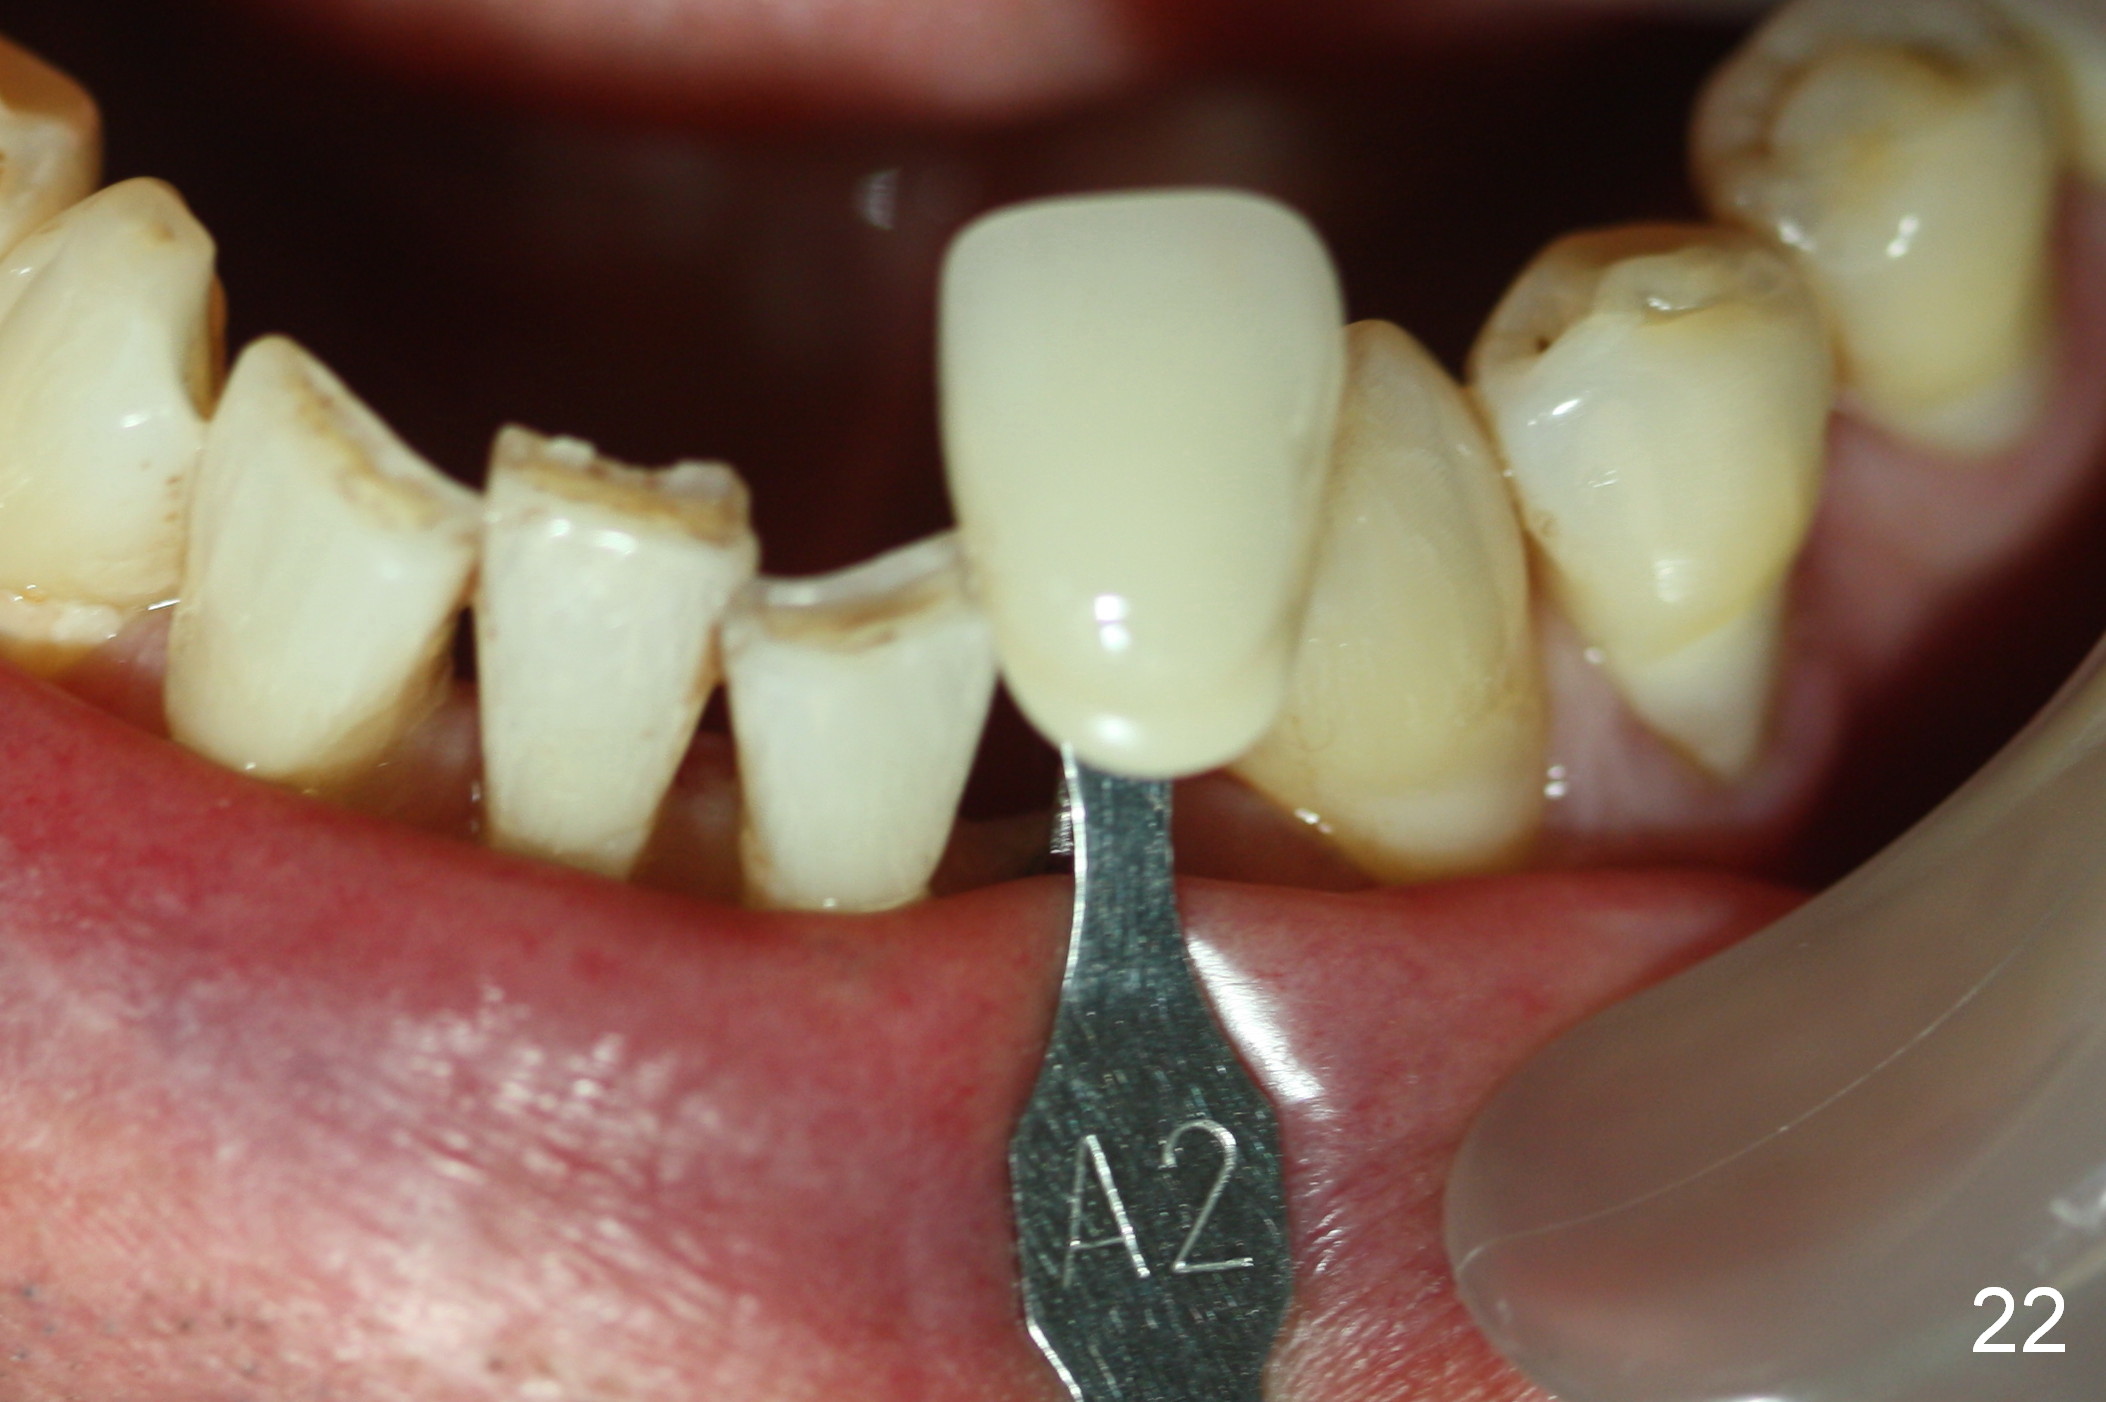

A 74-year-old man has several missing teeth (Fig.1). His 1st goal is to replace the lower left lateral incisor (Fig.2). The residual root has an apical lesion (Fig.3 *). To describe intraop findings, a CT image of a different patient is used (Fig.4 coronal section; B: buccal; L: lingual). After extraction, the buccal plate is found to be thin and low (Fig.5 arrowheads). A 1.5 mm pilot drill (Fig.6 red line) is used to initiate osteotomy in the lingual plate of the socket. Once the drill penetrates the lingual plate, the trajectory changes and the depth is 17 mm from the gingival margin (Fig.7). A PA is taken (Fig.8); it appears that the osteotomy can be extended more apically. When the pilot drill extends to 20 mm, there is sudden empty feeling. The lingual plate has perforated (Fig.9). A new osteotomy is established buccally (Fig.10 pink). To avoid buccal plate perforation, especially in the buccal undercut area (>), the coronal end of the drill has to be tilted buccally (<--). An angled abutment (3x20 mm, 15°) is placed (Fig.11,12). The abutment is modified (Fig.13,14) to accommodate an immediate provisional (Fig.15,16 P). Perio dressing is to be applied to prevent the bone graft from getting dislodged buccally (Fig.15). The dressing is in place 7 days postop (Fig.17).

Five months postop, the peri-implant space reduces (Fig.18). A keratinized band forms buccal to the implant (Fig.19 *). The provisional dislodges probably due to the buccal placement (Fig.20).